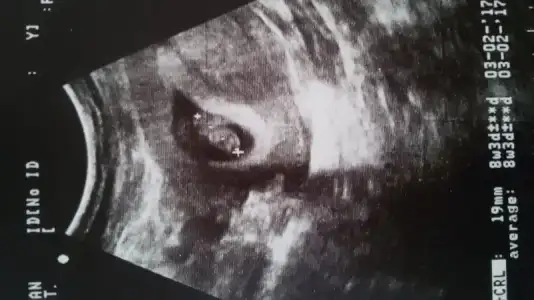

Merhaba benim içinde bi tahminde bulunabilirmisiniz 6 haftalık karından ultrason. Şimdiden teşekkürlerHavalianne__